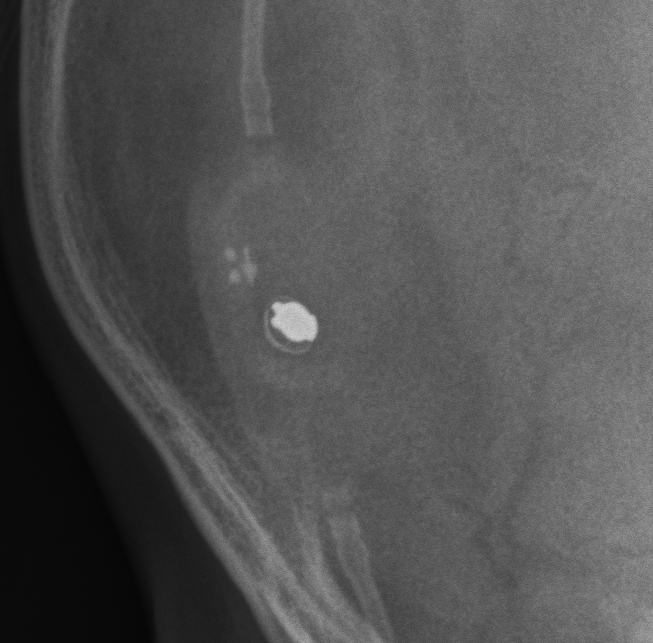

Non-Programmable Valves

Medtronic PS Medical Pressure Differential

Medtronic PS Medical Pressure Differential valves are non programmable csf shunt valves.

Codman Fixed Pressure Valve

Codman Fixed Pressure valves are non-programmable csf shunt valves.